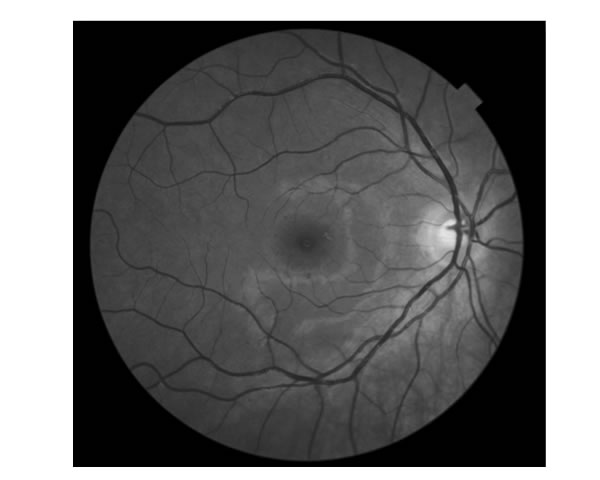

Slikanje očesnega ozadja OCT

Spremembe na očesnem ozadju se pogosteje pojavijo pri očesnih boleznih predvsem pri diabetesu, pri degeneraciji rumene pege (t.i. makule) , arterijski hipertenziji ter glavkomu (t.i. očesni pritisk).